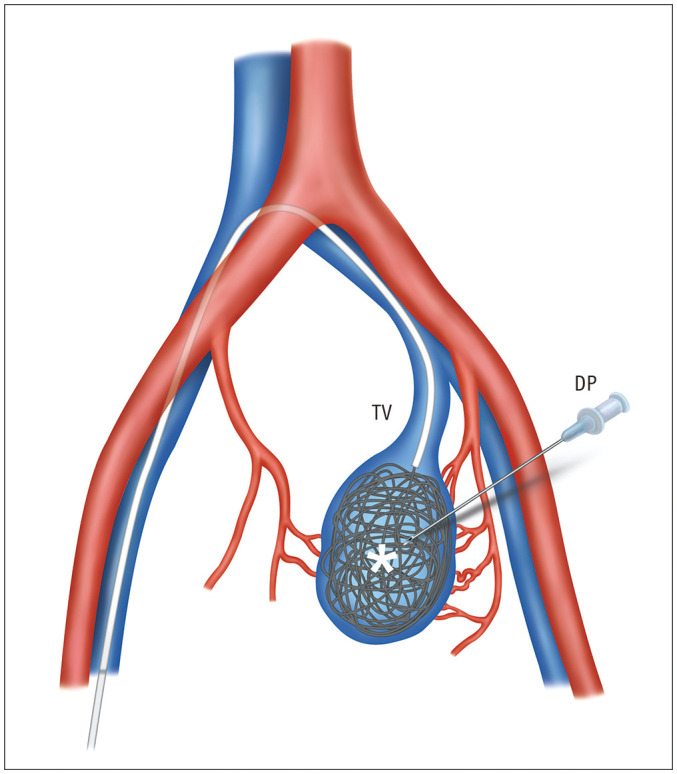

Materials and methods: A retrospective study was performed on 13 patients (median age, 43 years, range 20-62 years, 7 males) who underwent transvenous coil embolization for Type IIa pelvic AVM (characterized by multiple arterioles shunting to focal venous segments of a single draining vein) without the use of additional liquid embolic agents from March 2017 to February 2023. Treatment outcomes were analyzed based on clinical evaluations, post angiography findings, and follow-up CT.

Results: Fourteen procedures were performed on 13 patients. Except in one patient, all treatments were completed in a single session. Transvenous access was employed in 10 procedures, whereas direct puncture was used in four sessions. The embolization procedures used an average of 55.7 ± 58.5 coils (range, 7-238) and lasted an average of 127.3 ± 39.5 minutes. The technical success rate was 92.9% (of 13/14). All patients reported symptom improvement. Follow-up CT scans showed complete occlusion of the AVM without recurrence in ten of the 13 patients. There was one minor adverse event: a small retroperitoneal hemorrhage, likely related to direct puncture, which resolved spontaneously. No other adverse events were observed.